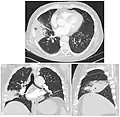

On a posteroanterior and lateral chest radiograph, an entire lobe will be radiopaque, which is indicative of lobar pneumonia.[5]